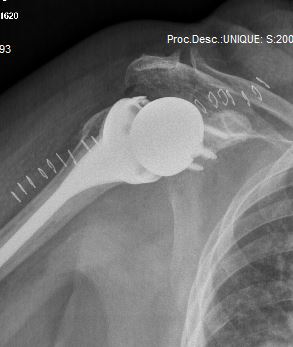

Reverse Total Shoulder Replacement

A reverse shoulder replacement is a unique replacement because in addition to replacing the ball and the socket with metal and plastic, the positions are “reversed”. The ball gets implanted where the socket usually is on the scapula. The socket gets implanted where the ball usually is on the humerus.

A reverse total shoulder replacement is necessary when the rotator cuff is torn and irreparable and the shoulder has osteoarthritis. Because there is no rotator cuff the shoulder ball and socket must be “reversed” so that the deltoid muscle can act as a lever to elevate the arm.